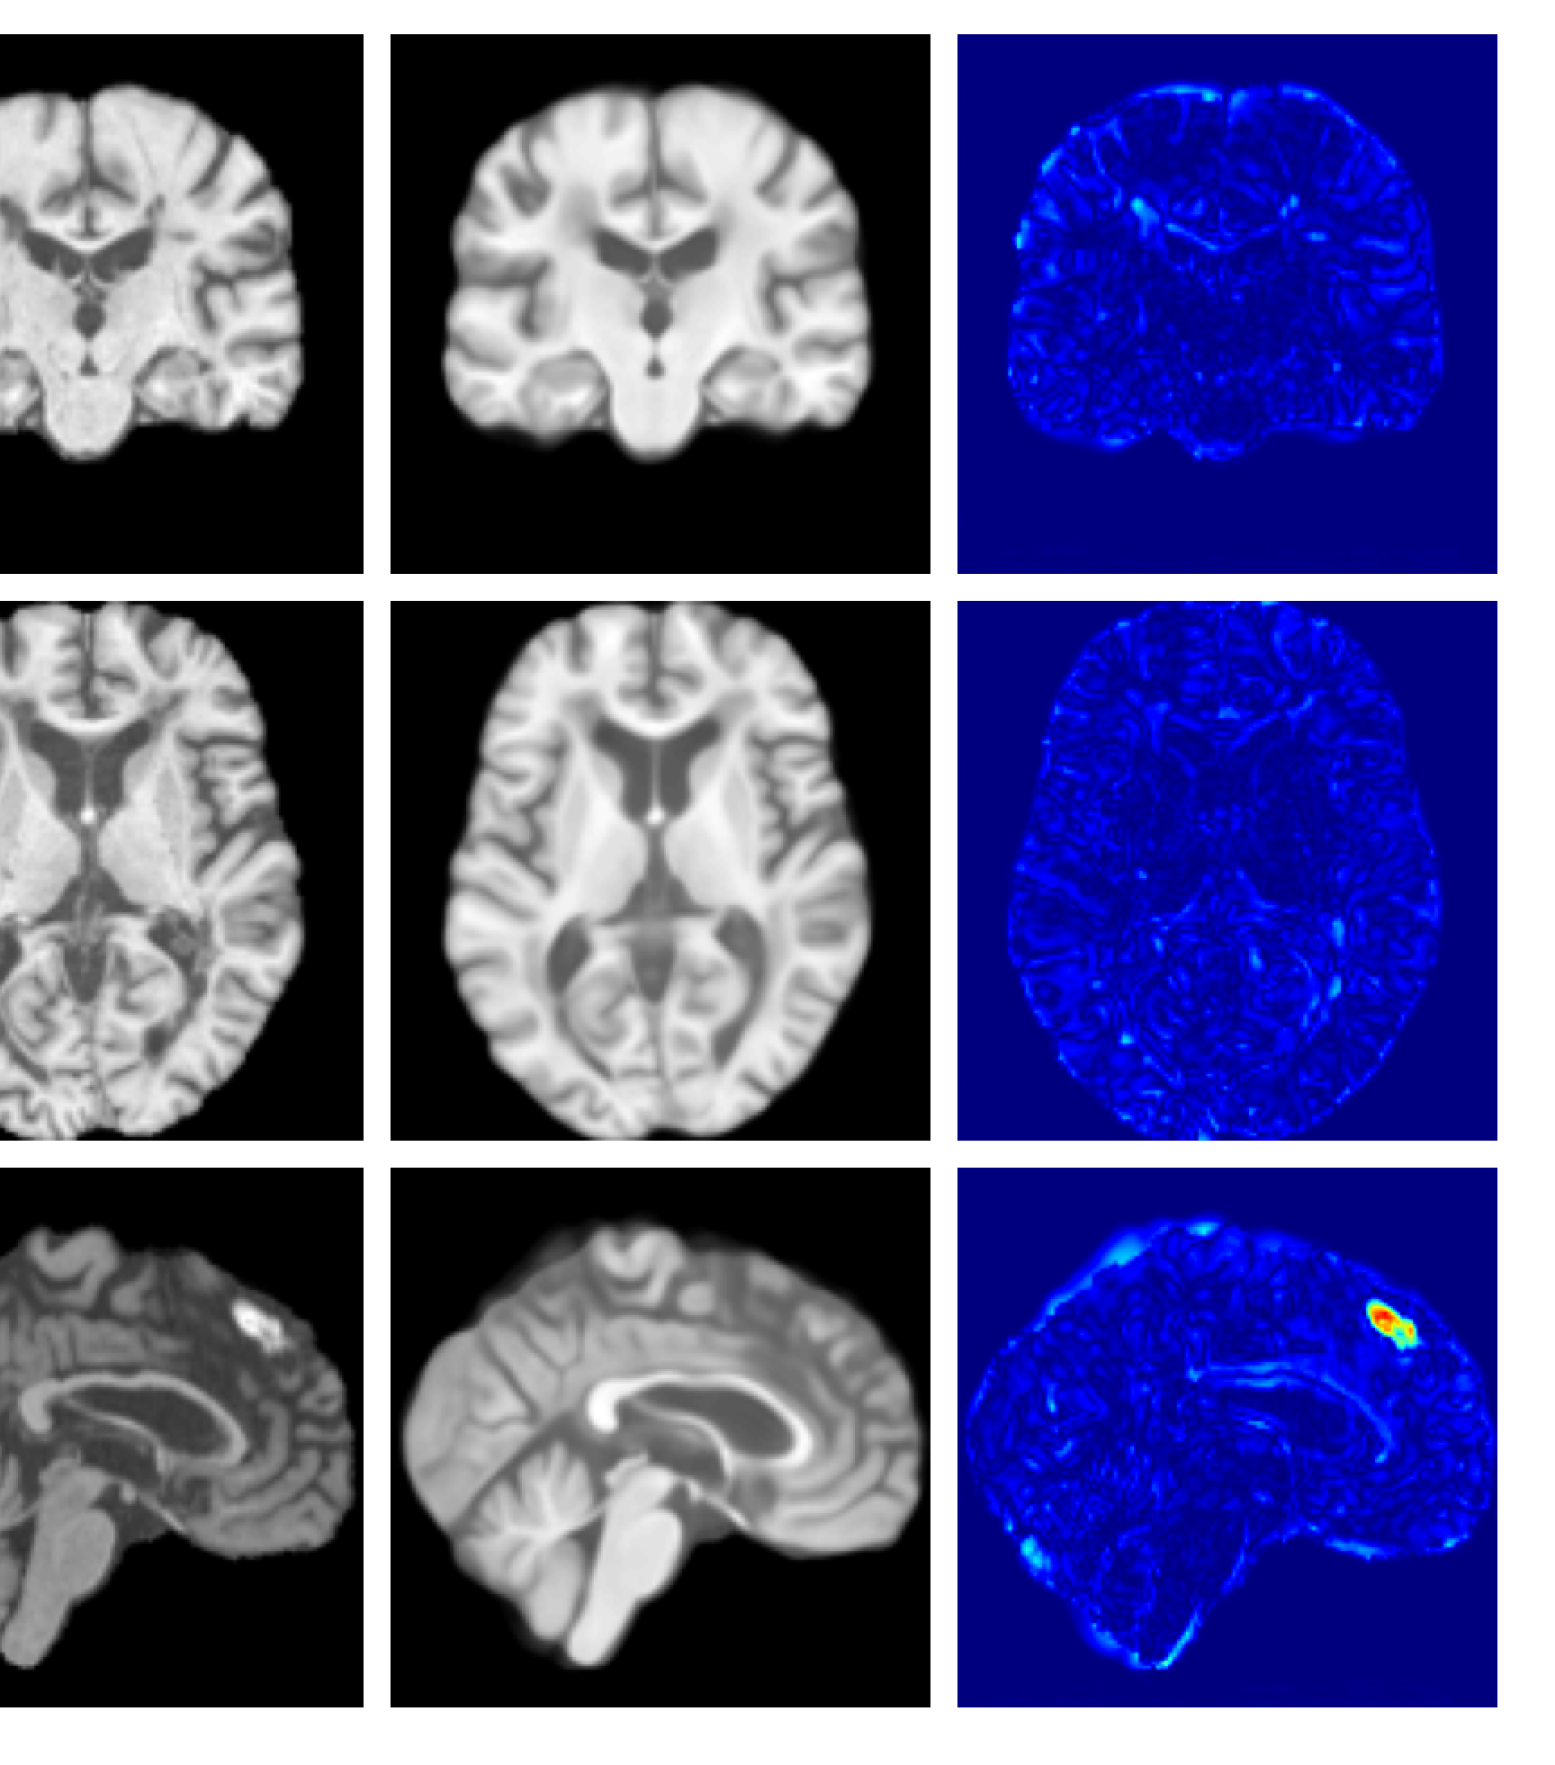

Figure 10: Example reconstructions and anomaly maps for an AD sample from the disease cohort of the ADNI dataset. We expect to see some inpainting of atrophied tissue whilst retaining the defining characteristics of the individual sample.

Figures 8 and 9 are enlarged versions of Figures 3 and 4 respectively, with the latter now including results from all compared methods. Figure 10 provides example reconstructions and anomaly maps for an AD subject from the ADNI disease cohort.